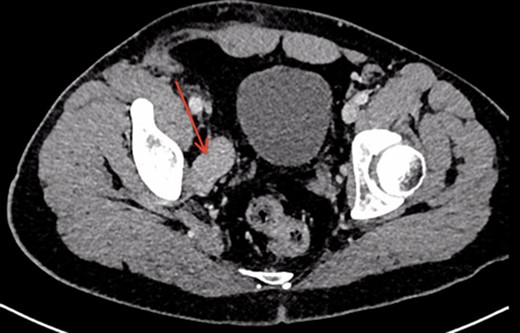

A 26-year-old man was referred to our vascular surgery tertiary referral service from his local hospital with leg size discrepancy (right > left) and prominent right leg varicose veins distally. He had lower urinary tract symptoms (frequency >30 times per day) for a year prior to presentation but had no leg symptoms in relation to his varicosities. His past medical history was of premature birth, as one of triplets, who spent a prolonged period on a neonatal intensive care unit. The patient thought he may have had a deep vein thrombosis in his right leg as a child. An MRI of his right thigh and pelvis demonstrated a 5 cm venous aneurysm (EIV), indenting the bladder, and generalized distal venous dilatation of both deep and superficial veins. He subsequently underwent venography, which confirmed an aneurysmal EIV, with massive collateral dilatation of trans-pelvic veins and complete occlusion of the right common femoral vein (CFV). A concurrent attempt at endovenous stenting was made, but was unsuccessful as the CFV could not be passed with a guide-wire and no alternate route was found possible. Further characterization by CT demonstrated a dilated and tortuous right internal iliac vein (IIV) feeding the aneurysm (Fig. 1). A multidisciplinary decision was made to proceed to operative repair, in light of the patient’s debilitating urinary frequency from the mass effect of the aneurysm. Pre-intervention venous severity scoring was not pursued as the patient’s symptoms were only bladder-related. The patient underwent an open aneurysmectomy via a Rutherford-Morrison incision, with concurrent right retrograde ureteric stent placement. Intra-operatively, a wide-necked aneurysm was confirmed to arise from the EIV (Fig. 2) in a saccular fashion. The aneurysm was clamped at the neck and closed with 3-0 Prolene (Ethicon, Inc., New Jersey, USA) leaving a normal calibre EIV (Figs 3 and 4). The IIV remained patent at the end of the procedure and a venous bypass was not performed. The patient recovered well post-operatively and was discharged home four days later, with removal of the ureteric stent prior to discharge. He has been followed up 6-monthly since and remains well at 2 years’ post-operatively. CT venogram has shown a good post-operative result, with no residual aneurysm (Fig. 5). The patient’s pre-operative lower urinary tract symptoms have improved. He did not develop any leg symptoms.

CT scan demonstrating right iliac vein aneurysm (5.7 cm) (red arrow) compressing the patient’s full bladder.